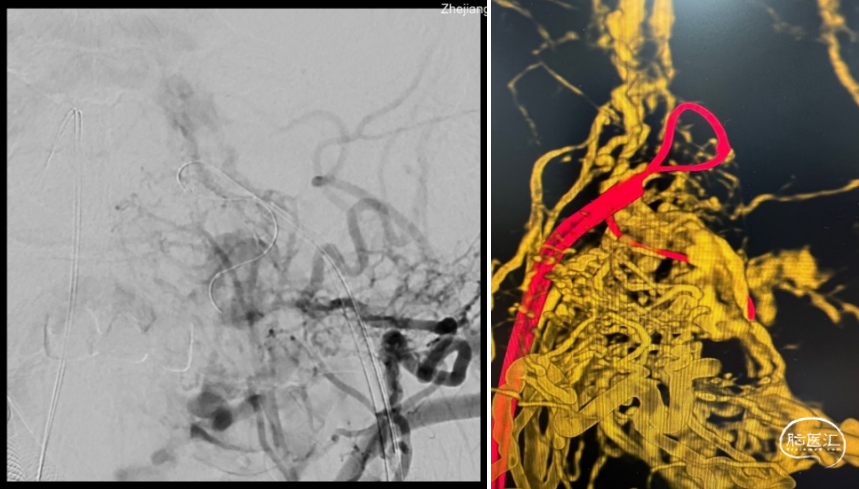

根据病史及当地医院辅助检查,诊断后颅窝硬脑膜动静脉瘘明确。分析当地医院MRA及血管造影结果,大致可判断该患者瘘口位于左侧舌下神经管或髁前汇区。详细读片可见左侧颈外动脉造影及椎动脉造影所示引流模式相同。入院后完善脑血管造影检查,并应用双容积影像后处理技术进行三维重建(图3)。便于进一步分析血管构筑,制定手术策略。

根据患者术前血管造影表现,该例病例确诊为左侧舌下神经管区硬脑膜动静脉瘘。分析其血管构筑特点:供血动脉为颈外动脉咽升动脉分支,椎动脉脑膜支,瘘口位于左侧舌下神经管区,经岩下窦向同侧海绵窦-海绵间窦-对侧海绵窦引流,并经髁前静脉向椎旁及椎管内静脉引流。患者有显著的搏动性耳鸣症状,且引流静脉具有出血风险,手术指征存在。笔者所在的中心既往诊疗的病例表明,舌下神经管的引流模式多种多样,但多数可见髁前静脉向岩下窦汇合。该患者亦有此静脉引流通道(图3黄色箭头所示),因此介入栓塞的路径上可考虑经要岩下窦-髁静脉路径。